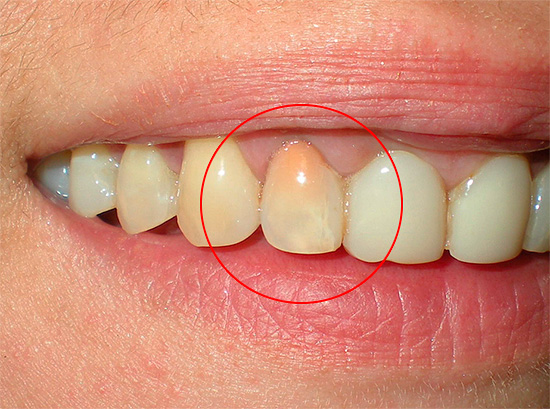

Se il messaggio cavità cariata con una camera pulpare, dove si trova il "nervo" collassante, buono e non ostacolato, quindi con la polipite cancrenosa non possono esserci sintomi di dolore. In tali casi, il paziente indica solo un cambiamento nel colore del dente - l'aspetto di una tinta grigiastra.

Foto di un dente con polmonite gangrenosa cronica: un'ombra grigia malsana è chiaramente visibile:

Quando si esamina un dente, la sua tinta grigia colpisce di solito in presenza di una cavità cariata che si estende in profondità nella bocca dei canali radicolari. Quando si sondano, si nota la presenza di una grande quantità di dentina ammorbidita cariata e la penetrazione profonda dall'estremità acuta della sonda nella bocca dei canali radicolari è spesso dolorosa, sebbene a volte si verifichi dolore quando viene uccisa una parte della polpa radicolare.